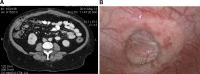

Introduction: Ventral hernias are common and repair with mesh has been shown to reduce recurrence. However, synthetic mesh is associated with a risk of infection. Biologic mesh is an alternative that may be less susceptible to infection. Typically, the sublay position is preferred for mesh placement but this technique takes longer and has not been shown to have a lower recurrence rate than an onlay mesh. The aim of this study was to evaluate the outcome of complex ventral hernia repair using a porcine non-cross-linked biologic mesh onlay.

Methods: A retrospective chart review was performed of all patients that had a ventral hernia repair with biologic mesh from January 2009 to March 2012. The operative procedure in all patients was an open repair with primary fascial closure (if possible) with or without external oblique component separation and porcine biologic mesh onlay.

Results: There were 22 patients that had a ventral hernia repair, 19 primary and 3 recurrent. The majority were men, had hernia grade 3 or 4, and developed the hernia after an esophagectomy or gastrectomy for cancer. All but one had primary closure with a porcine biologic mesh onlay. One patient was bridged for loss of domain. A bilateral external oblique component separation was added in 16 patients (73 %). The median hospital stay was 7 days. There were two superficial wound infections, one with exposed mesh, but no patient required mesh removal. A seroma requiring intervention developed in 6 patients (27 %) and resolved with pig-tail drainage. At a median follow-up of 7 months, there has been no hernia recurrence apart from the patient that was bridged.

Conclusions: Porcine non-cross-linked biologic mesh overlay has excellent short-term results in patients at increased risk for mesh infection. No patient required mesh removal, and there have been no recurrent hernias in patients with primary fascial closure. Biologic bridging is not effective for long-term abdominal wall reconstruction.